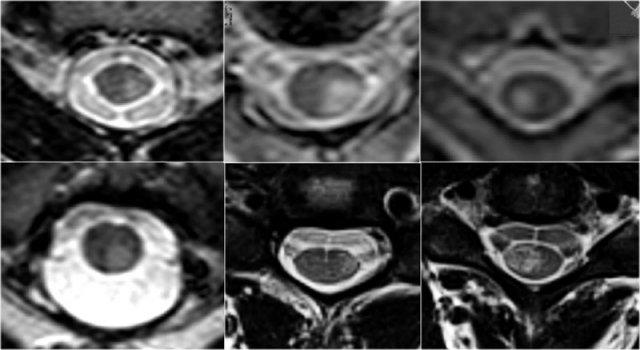

Hình ảnh mặt cắt ngang rất hữu ích trong chẩn đoán phân biệt.

Cần có hình ảnh độ phân giải cao.

Đánh giá mức độ tổn thương (cả hai nửa hay không), vị trí tổn thương và hình dạng của tổn thương.

MS thường có hình dạng tam giác và chủ yếu nằm ở phía lưng hoặc phía bên.

Tuy nhiên, MS có thể có hình ảnh đa dạng và đôi khi hiếm gặp có thể tổn thương toàn bộ đường kính ngang hoặc chỉ phần trước. - Thiếu máu cục bộ do nhồi máu động mạch thường nằm ở phần trước, nhưng có thể tổn thương toàn bộ đường kính ngang.

- Viêm tủy cắt ngang và Viêm tủy thị thần kinh thường tổn thương toàn bộ tủy sống.

Trên hình ảnh cắt ngang, các tổn thương MS thường có hình tròn hoặc hình tam giác và nằm ở phía sau hoặc phía bên.

Vậy chúng ta có thể loại trừ MS nếu tổn thương nằm ở phía trước không?

Tiếc là không thể.

MS là bệnh “bắt chước vĩ đại” và cũng có thể nằm ở phía trước như ở bệnh nhân này, người có tổn thương ở vị trí điển hình (mũi tên xanh) nhưng cũng có tổn thương ở phía bụng của tủy (mũi tên đỏ).

Điều này không phổ biến, nhưng bạn không thể loại trừ MS.